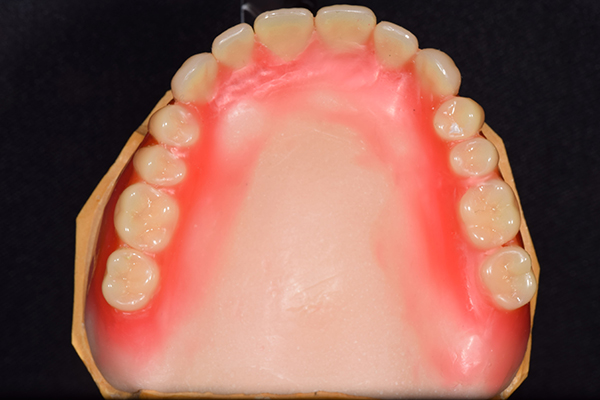

入れ歯は極力薄くするために金属を使用しました。しっかり噛める様にするため、ノンメタルクラスプデンチャーにはしませんでした。

上の入れ歯(表)

上の入れ歯(裏)